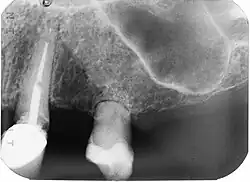

X-Ray of affected tooth (incisor 9, left).

The pathophysiology of root resorption is not completely understood. It is postulated that osteoclasts are the cells responsible for the resorption of the root surface.[7] Osteoclasts can break down bone, cartilage and dentin.[8]